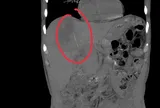

Ngày càng nhiều người mắc bệnh gan, bác sĩ cảnh báo: Có 5 món âm thầm hại gan, ngon mấy cũng nên hạn chế- Ảnh 1.

Ảnh minh hoạ